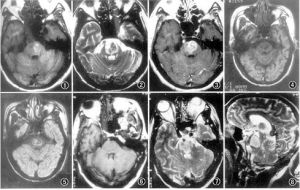

腦橋中央髓鞘溶解症影像圖流行病學

診斷:慢性酒精中毒、嚴重全身性疾病和低鈉血症糾正過快的患者,臨床上在數天之內突然發展為四肢癱瘓,假性延髓性麻痹和閉鎖綜合徵,就應考慮腦橋中央髓鞘溶解症的診斷。MRI有助於確診。實驗室檢查

本病應與腦橋基底部梗死、腫瘤和多發性硬化等鑑別。MRI顯示CPM無顯著占位效應,病灶對稱,不符合血管分布特徵,隨病情好轉可恢復正常。治療